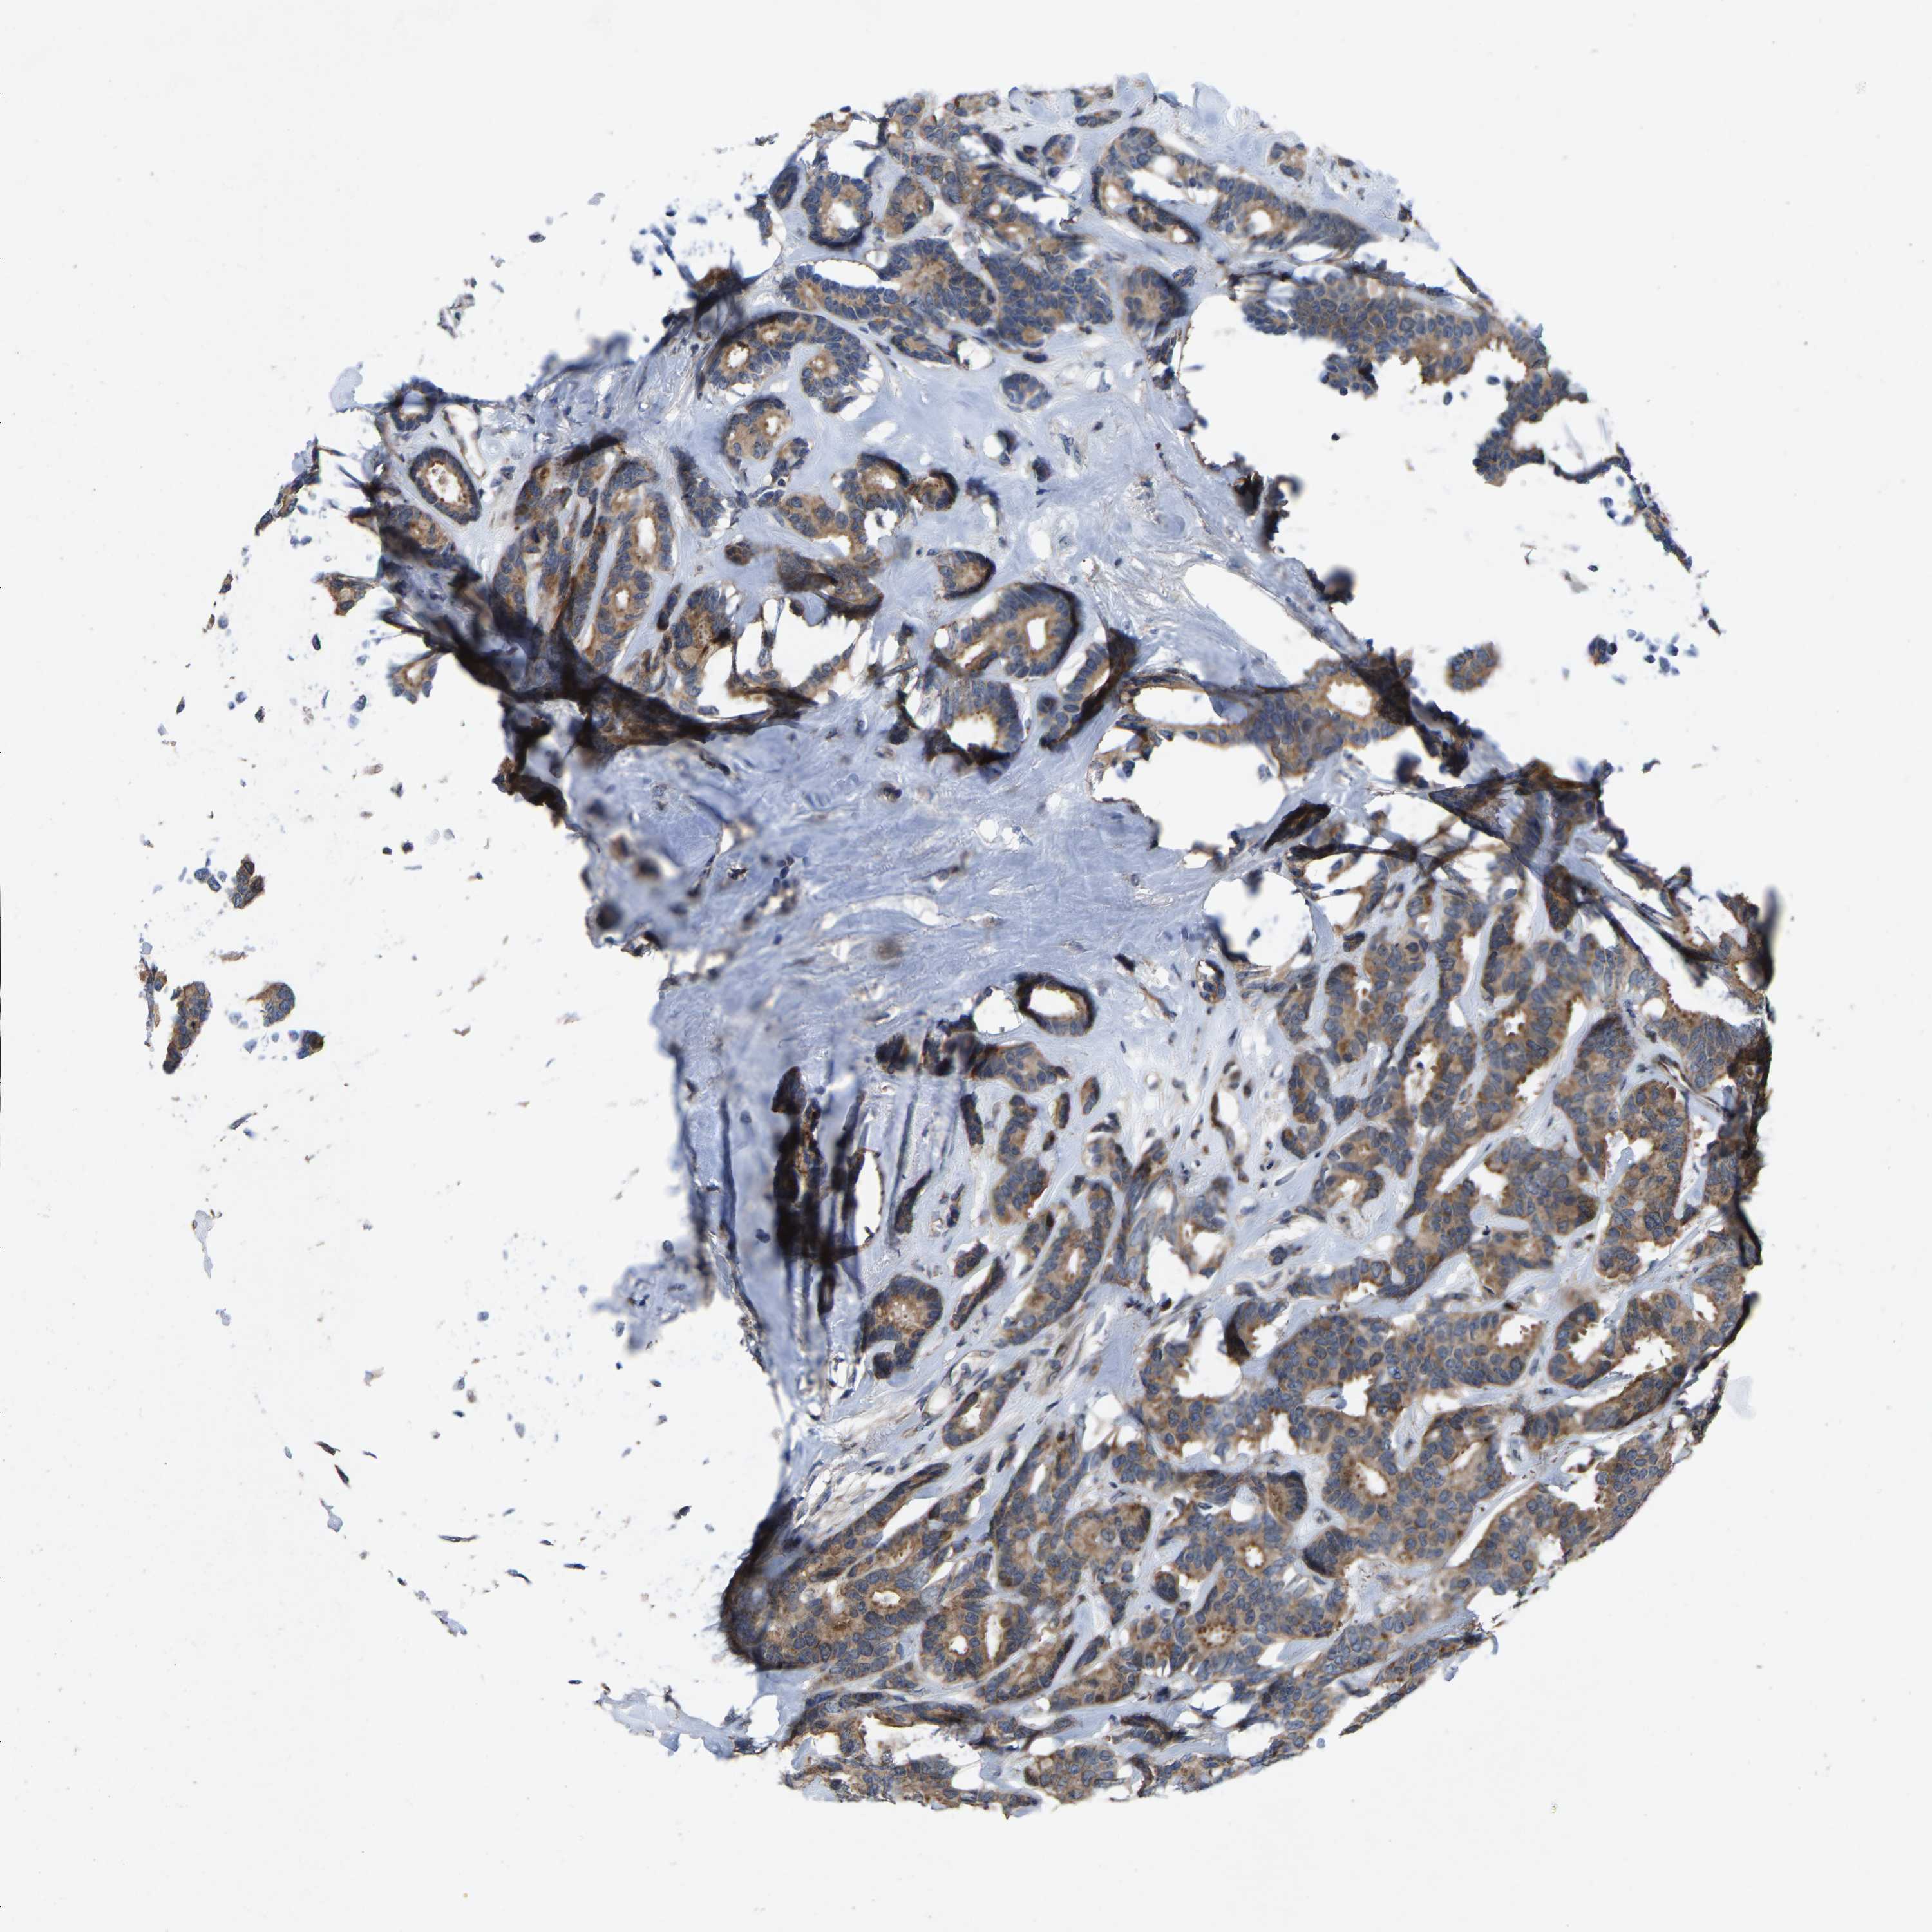

CANCER BREAST CANCER Show tissue menu

BRCA TCGA BRCA VALIDATION PROTEIN EXPRESSION